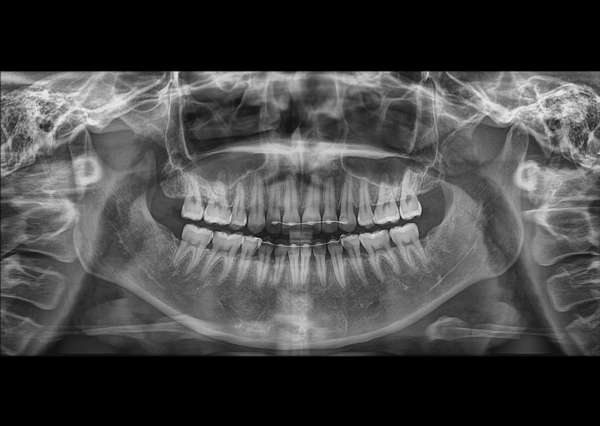

Trong kỷ nguyên nha khoa kỹ thuật số, chẩn đoán dựa trên phim 2D đã không còn đủ để kiểm soát các rủi ro giải phẫu. Papaya 3D Plus (Genoray – Hàn Quốc) là hệ thống hình ảnh 3 trong 1 (CBCT, Panorama, Cephalometric) được thiết kế để cung cấp dữ liệu lâm sàng với độ nét cao, không biến dạng, giúp Bác sĩ:

Xác định rõ ràng đường đi của ống thần kinh răng dưới (IAN) và ranh giới xoang hàm.

Phát hiện các tổn thương nội nha, nang nứt chân răng mà X-quang thường bỏ sót.